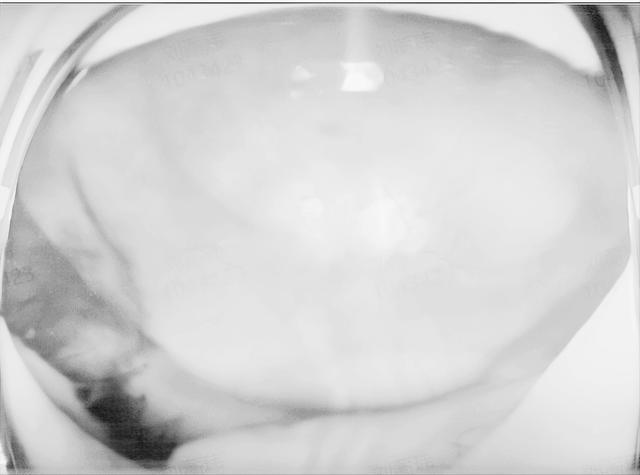

两例患者最终均实现视网膜解剖复位,两位患者术后前房恢复透明,人工晶体位置稳定,患者1的矫正视力恢复到0.15,尽管SCH的总体预后仍不乐观,但及时规范的治疗可最大限度保留,眼球结构和残存视力。

(▲患者2术后眼前段及眼底照)